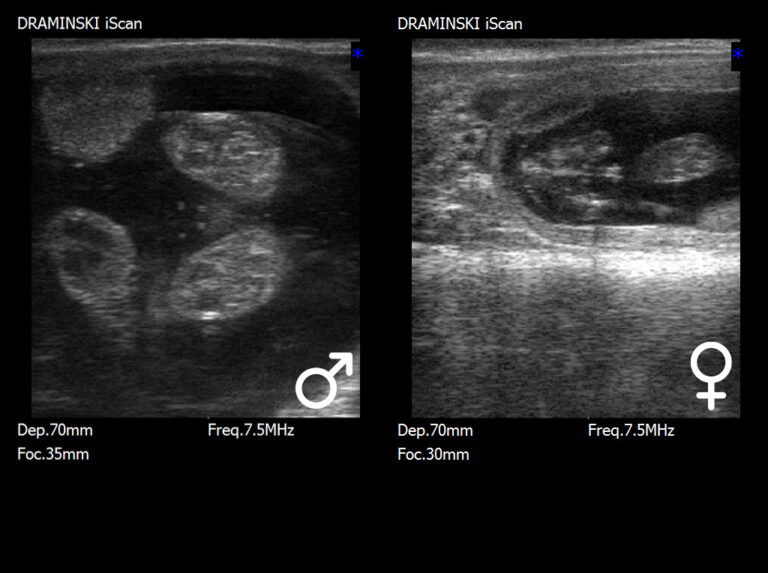

Przenośne ultrasonografy weterynaryjne

do kompleksowej diagnostyki małych

i dużych zwierząt.

Urządzenia elektroniczne wspierające

hodowlę i rozród zwierząt gospodarskich

oraz psów.